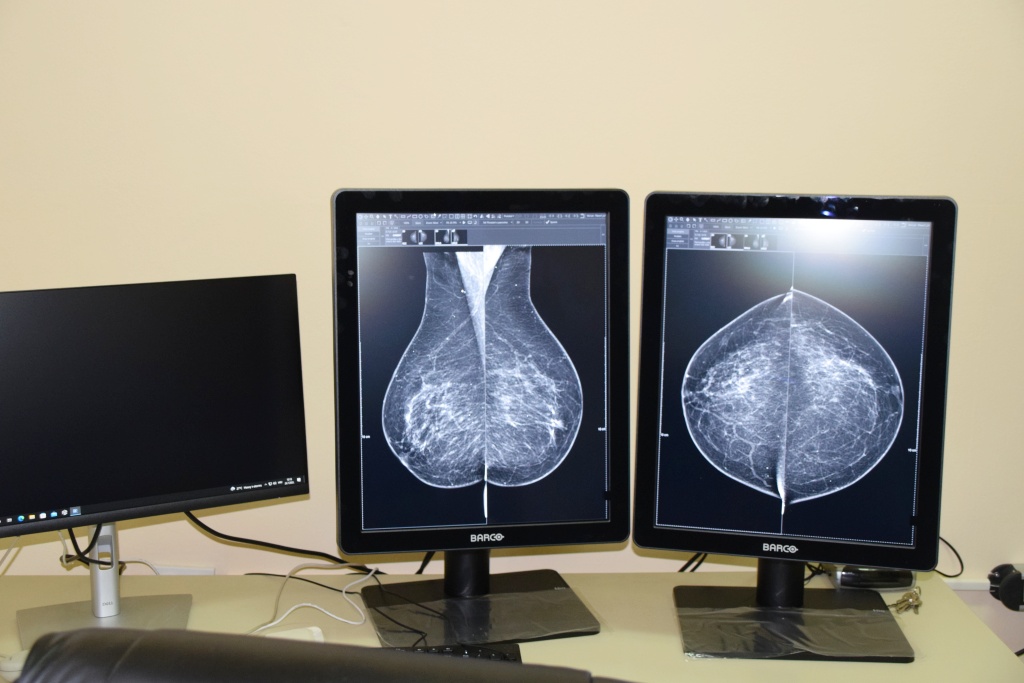

Tom je prilikom, na Odjelu radiologije, zamjenica županice razgledala novi mamograf, kojeg je Karlovačka županija nabavila za potrebe OB Ogulin i ovdašnjih pacijenata. Novi uređaj, jedan od najmodernijih na tržištu, isporučila je tvrtka Siemens te je od nedavno pušten u rad i na njemu se već obavljaju ugovoreni pregledi.

Ovaj digitalni mamograf sa tomosintezom je uređaj čija ukupna vrijednost iznosi 1.087.500,00 kn, a njegovu nabavu je financirala Karlovačka županija putem decentraliziranih sredstava u 2022.godini.

Takav uređaj omogućava bolju analizu, kvalitetniju sliku (3D sliku) što je posebno važno kod ranog otkrivanja raka dojke, a što je i cilj Nacionalnog programa ranog otkrivanja raka dojke.